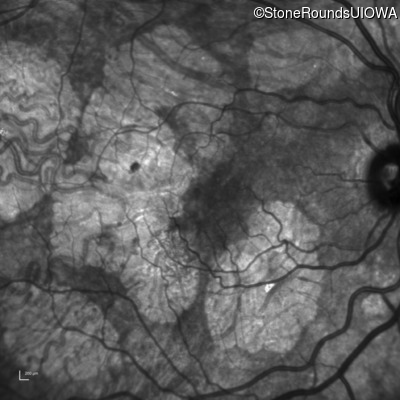

Infrared Fundus Photograph - Right - 20/40 -2

Exemplar

Infrared Fundus Photograph - Left - 20/40 +1